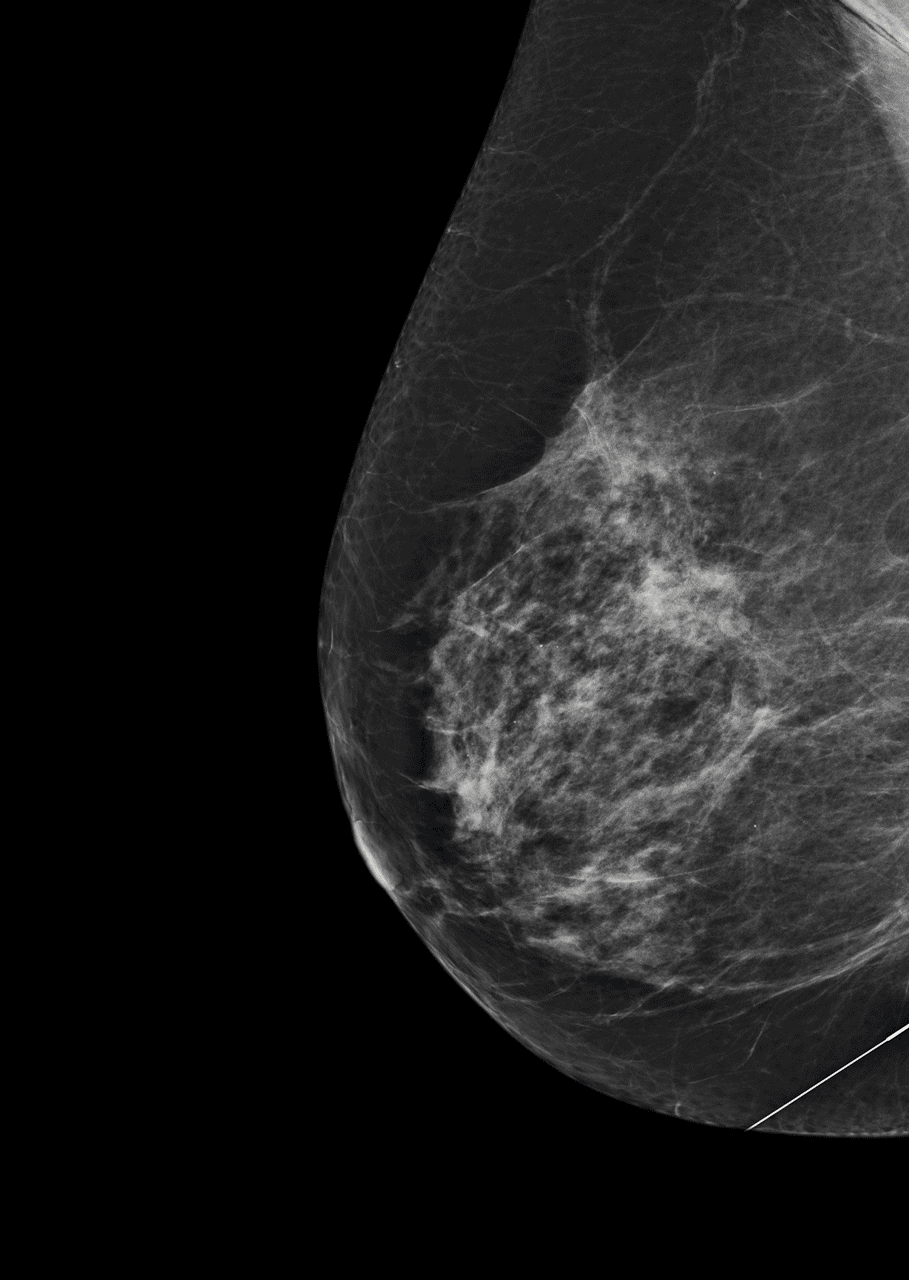

As the team started processing thousands of samples, just like algorithms in digital communication, they improved. A study of the technology found common disease-driving mutated genes detected by Guardant360 in breast, lung, colorectal, and other cancers were also present in 94-100 per cent of the solid tissues extracted from trial participants.

Guardant has processed over 15,000 liquid biopsies and 50 tumour types to improve performance and has helped doctors discover the presence of cancerous tumours before they have presented symptoms.

Once cancer signals are unlocked, at an extremely high fidelity for each type, they are classified and grouped into different sub-sets of cancer. As specificity and sensitivity gets better, the company will classify more sub-types of cancer and start decoding and unlocking signals for Stage One, Stage Two and recurrent cancers.